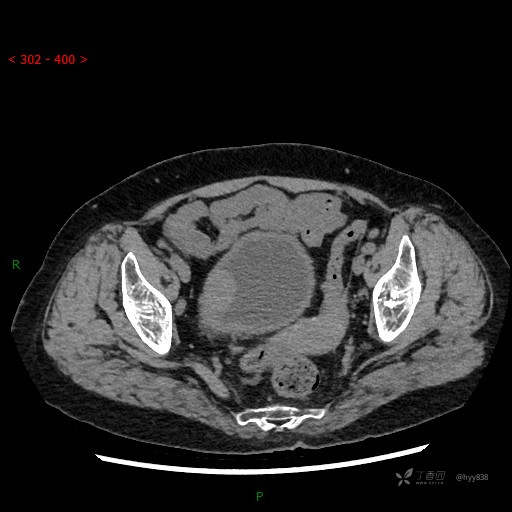

增强(2022.11.1)